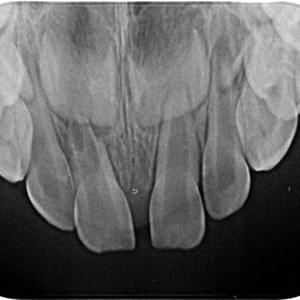

Radiografías

Periapicales, bitewing oclusales

Equipo intraoral

Sirona Heliodent Plus

Colimación rectangular que disminuye en 92% la dosis necesaria, cumpliendo las mas estrictas normas europeas.